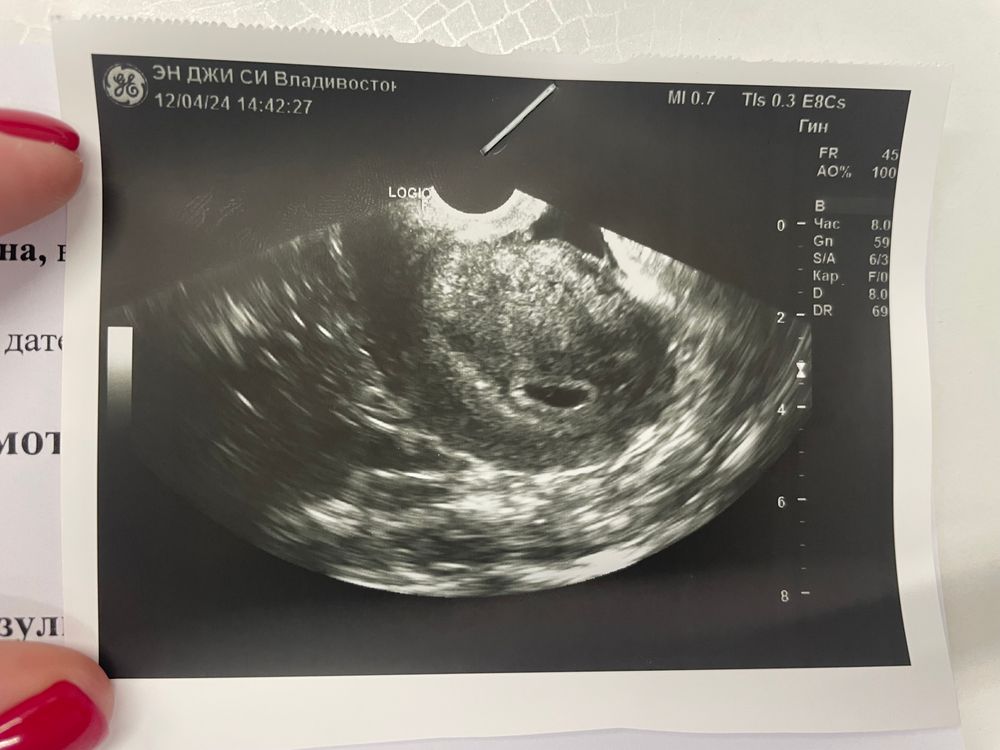

ПЯ 10мм ЖМ 3мм 20дпп и первое узи😊😊😊

Ой девочки дождалась, вчера была на 20дпп у ре на узи) пока конечно Буси не видно, рано понимаю) не тороплю ее😊пусть растет. ПЯ 10мм ЖМ 3мм, ре сказала все хорошо все соответствует и все устраивает, тьфу тьфу🤞🏼🤞🏼🤞🏼 пойдем теперь на 32дпп на узи смотреть Бусю и слушать сб) сказала себя не накручивать и идти расти дальше.

А желточный мешочек это бусинка в серединке? Мне ре сказала, что кроме пя ничего нет у меня 18дпп, а мне по фотке казалось что тоже бусинка есть в уголочке или меня глючит🙈?

Ирина, Ира да жм это колечко в серединке. Мне тоже кажется что у вас есть оно просто расплывчатое